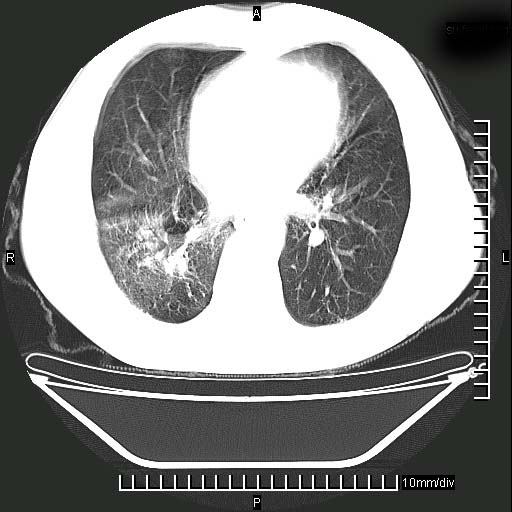

既往肺结核,近10几天,咳嗽,咳痰,右侧胸痛,疼痛较明显,右上肺斑块考虑结核灶胸膜粘连,增强,可惜动脉期没有定好,未见强化,可延迟4分后又见较明显强化,中心见低密度影,如果说结核是边缘强化,可这个灶强化的面积挺大的,让人很挠头。

动脉期